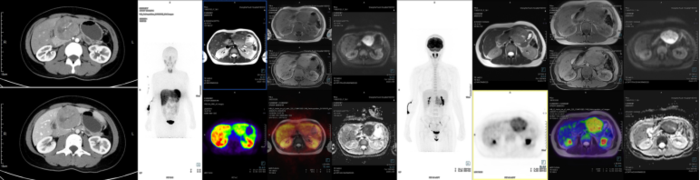

腺泡细胞癌(ACC),是比较少见的胰腺恶性肿瘤,也很容易和神经内分泌肿瘤混淆。好发于中老年人,没有特殊的临床症状,少数可伴有AFP升高,表现为多结节状或分叶状,体积大者中央可以发生囊变坏死,增强后中低度强化、一般低于正常胰腺组织,与周围组织分界较清,此点不同于胰腺导管癌。腺泡细胞癌高度恶性、但预后比胰腺导管上皮腺癌好。病理特点是具有多种结构模式的致密细胞肿瘤,肿瘤细胞巢周围有许多小血管,间质缺乏纤维反应,常见血管侵犯。肿瘤细胞核呈泡状,核仁明显,免疫组化通常Trypsin阳性。腺泡细胞癌通常生长抑素受体显像为阴性。(下图为一例胰头腺泡细胞癌临床资料,本例可见肿瘤代谢不高,肿瘤中心DOTATATE未摄取,边缘局灶摄取增高),该肿瘤很讨厌,能做的就是手术,化疗没什么好的方案。

胰母细胞瘤,是一类罕见的胰腺外分泌恶性肿瘤,占所有胰腺外分泌恶性肿瘤<1%,多见于婴儿和儿童,但也会出现在成人中,男女比例接近。病变可以发生在胰腺各个部位,通常为实性肿块,约30%的胰母细胞瘤会分泌AFP。组织学上,胰母细胞瘤由可能混杂腺泡、导管、胰岛细胞的原始小多角形或梭形细胞组成,免疫染色可查见由腺泡、导管或内分泌标志物。原始细胞中可见特征性“鳞状”小体。成人胰母细胞瘤似乎较儿童差,局限性肿瘤手术切除为首选。胰母细胞瘤在CT扫描下显示为一巨大的边界清楚的分叶状肿瘤,可伴有钙化。(下图为一例成人胰母细胞瘤病例,需要注意肿瘤少量表达SSTR2A,故68Ga-DOTATATE PETMRI显示DOTATATE摄取增高,易与神经内分泌肿瘤混淆)